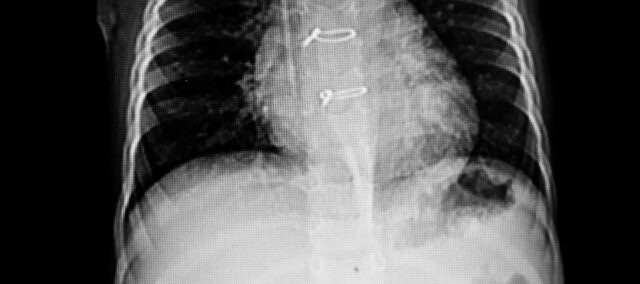

Det primære utfallet var sternal separasjon målt ved hjelp av ultralyd. Avstanden mellom de to halvdelene av brystbenet ble kvantifisert og punktet med størst separasjon ble markert. Som et sekundært resultat ble Sternal Instability Scale brukt som evaluerer sternal integritet fra grad 0 (klinisk stabilt brystben) til grad 3 (betydelig bevegelse eller separasjon). Målingene ble oppnådd ved baseline (7. dag postoperativt) og uke 4.

Trettiseks kvinner som hadde akutt sternal ustabilitet bekreftet ved ultralyd ble inkludert. Grunnlinjekarakteristikkene viste to sammenlignbare grupper. De hadde en sternalseparasjon ved baseline på 0,23 cm

Det primære resultatet av sternal separasjon ved uke 4 var 0,13 cm i forsøksgruppen og 0,22 i kontrollgruppen. Dette ga en forskjell mellom grupper på -0,09 cm (95 % KI 0,07 til 0,11) til fordel for intervensjonsgruppen som utførte trunkstabiliserende øvelser etter sternotomi.